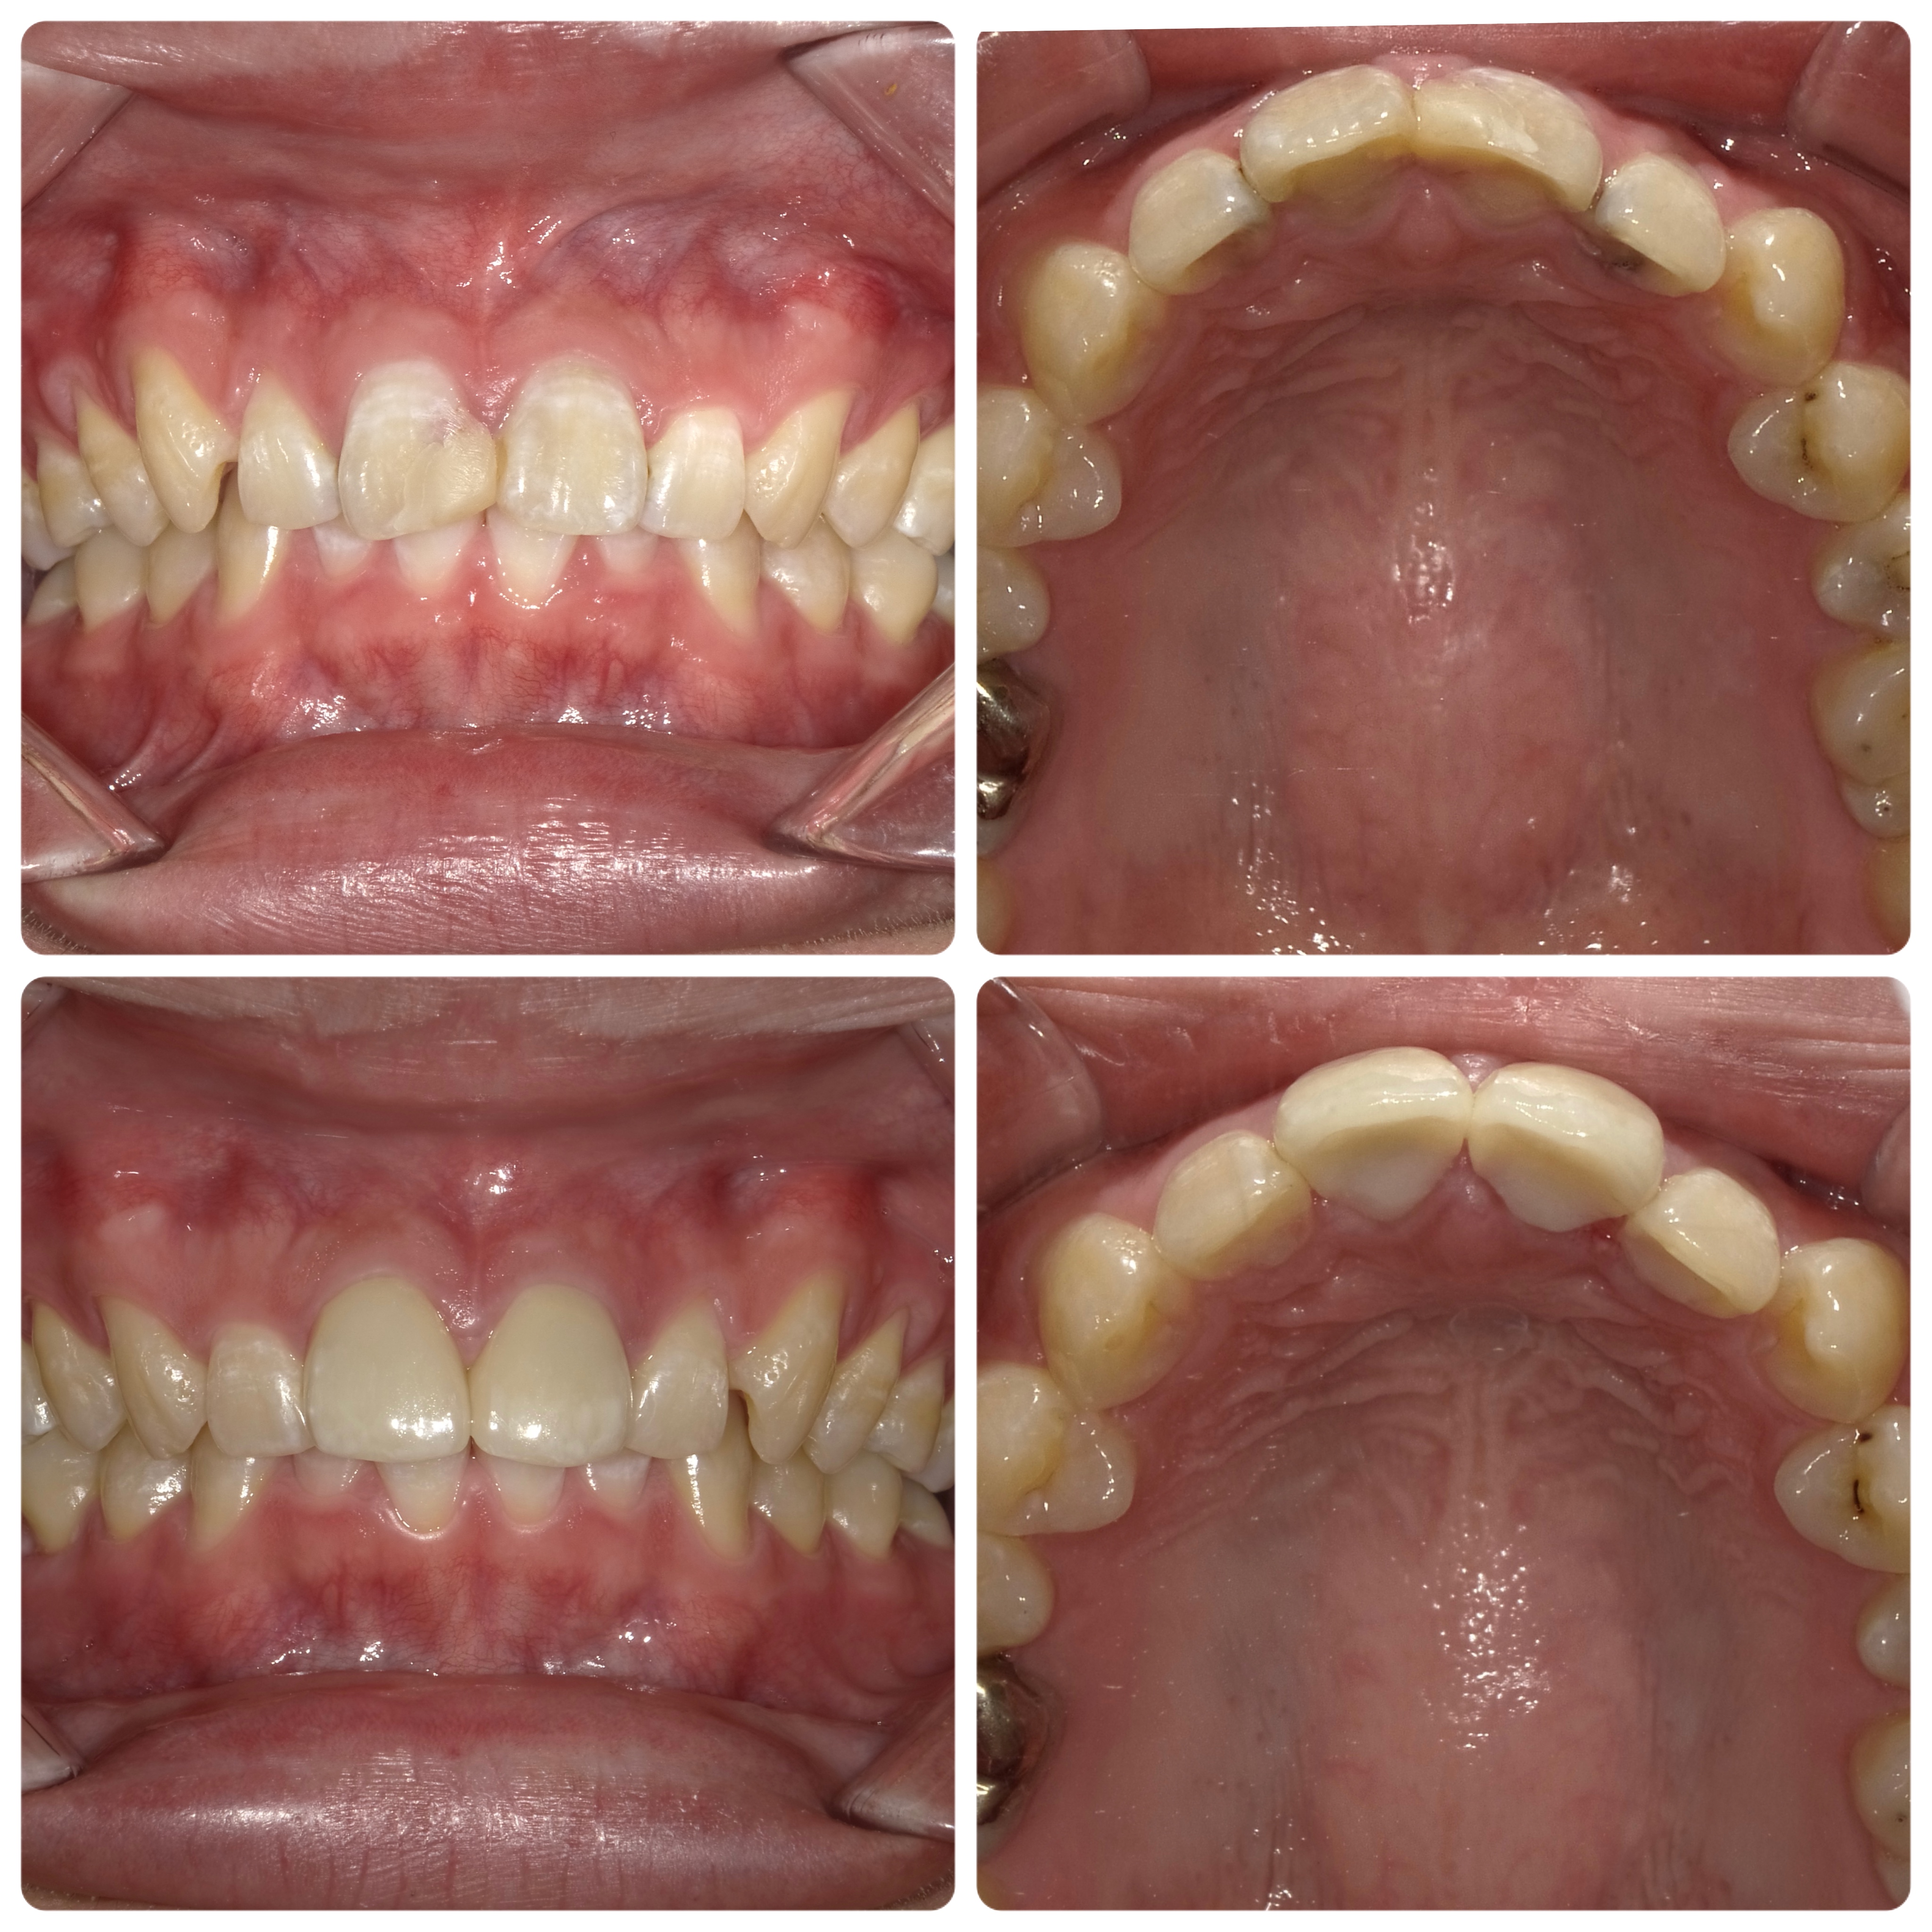

抜歯と言われた歯を残しました

2023/09/26症例